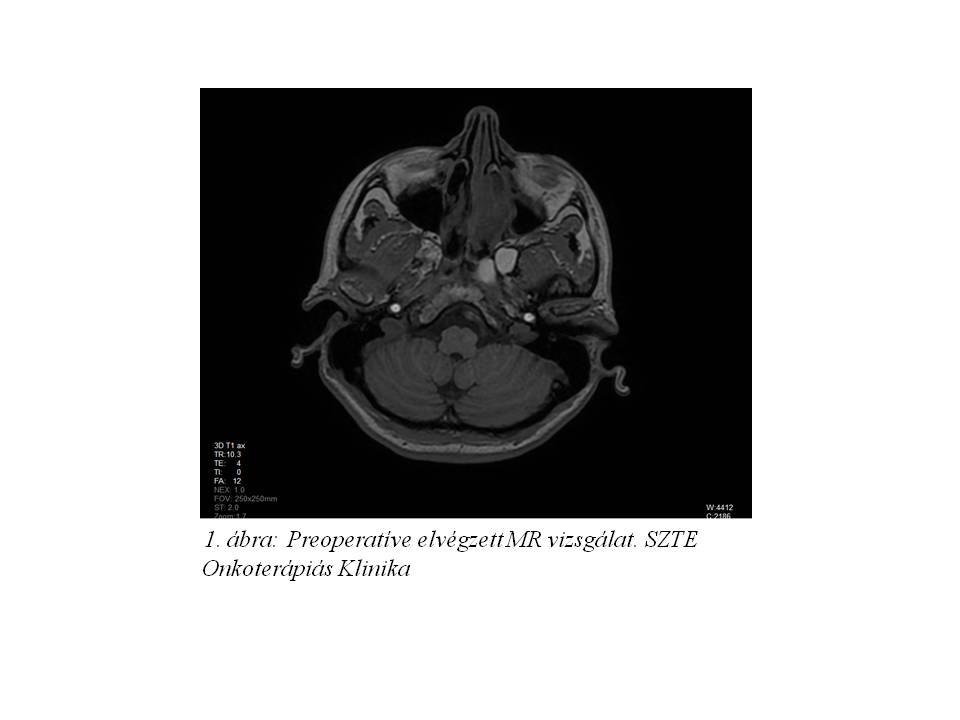

Panaszai kapcsán fül-orr-gégészetei szakvizsgálat, majd CT és MR vizsgálat történt. A felvételeken a lamina cribrosából kiinduló és mind a nyálkahártyát, mind a durát elemelő, az orr- és a koponyaüregbe egyaránt beterjedő terime ábrázolódott, amely a sinus sphenoidalist lezárta, ezzel jelentős folyadékgyülemet is okozva. (1. ábra, 2. ábra, 3. ábra). Fizikális vizsgálattal a beteg neurológiai statusban durva eltérés nem igazolódott.